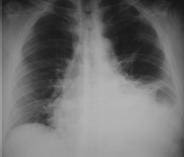

Acudió al Servicio de Urgencias del Hospital Universitario de La Samaritana en Bogotá (Colombia), a donde ingresó con distensión abdominal y disminución de los ruidos intestinales; no tenía antecedentes médicos, quirúrgicos ni de trauma. Se inició el manejo con líquidos endovenosos. El cuadro hemático fue normal y la ecografía abdominal demostró líquido libre en la cavidad peritoneal. Se tomó una radiografía de tórax (figura 1) que sugirió una hernia diafragmática.

FIGURA 1. Radiografía de tórax. Ángulo costofrénico izquierdo obliterado por la presencia de líquido pleural; no se descarta hernia diafragmática.